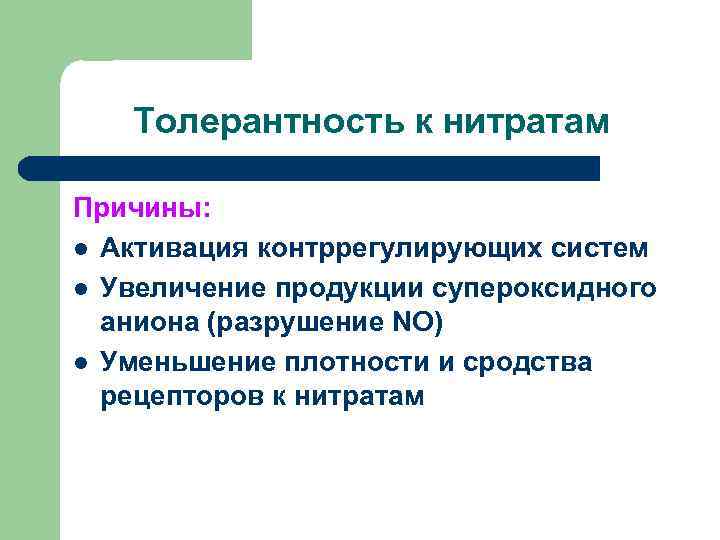

Толерантность к нитратам Причины: l Активация контррегулирующих систем l Увеличение продукции супероксидного аниона (разрушение NO) l Уменьшение плотности и сродства рецепторов к нитратам